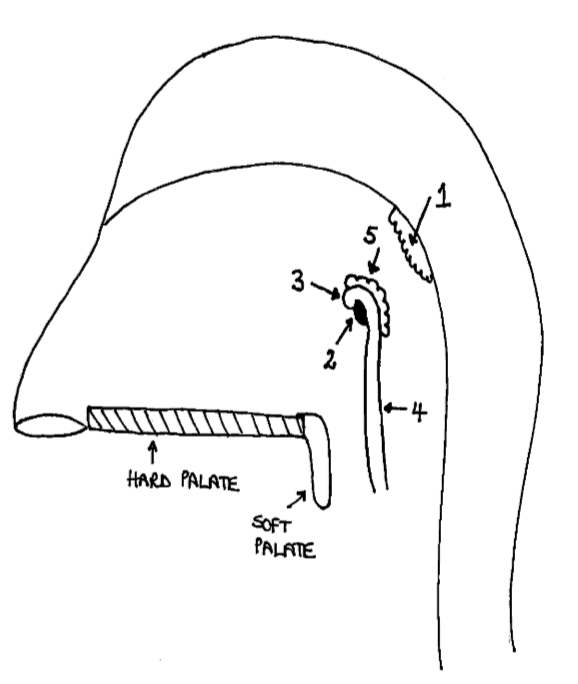

What is the anterior wall of 1?

posterior nasal choanae

What is the roof of 1?

body of sphenoid and basilar part of occipital

What is the posterior wall of 1?

anterior arch of atlas covered in pharyngobasilar fascia

What is the floor of 1?

soft palate

What is 1?

pharyngeal tonsil

What is 2?

pharyngeal opening of pharyngotympanic tube

What is 3?

tubal elevation

What is 4?

salpingopharyngeal fold

What is 5?

tubal tonsil